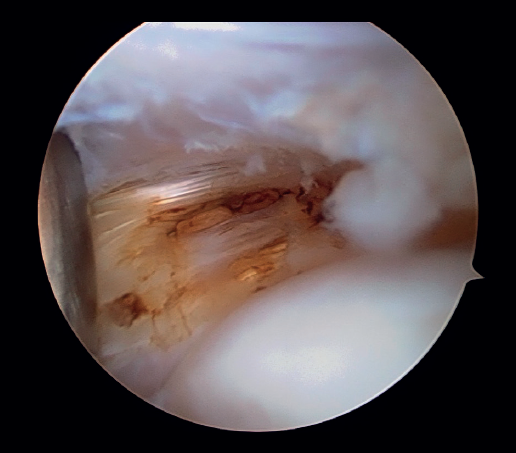

Posteriormente, se realiza la capsulotomía parcial lateral con sinoviotomo o vaporizador, hasta conseguir apreciar el ECRB (Figura 7). Una vez que se consigue su visualización, mediante el sinoviotomo y el vaporizador, se procede a la tenotomía de la inserción del ECRB en el epicóndilo, así como del tejido degenerativo tendinoso asociado (Figura 8). La liberación del tendón del ECRB debe limitarse a una zona anterior al eje central de la cabeza radial con el codo a 90°, para preservar la integridad del ligamento colateral lateral.

Figura 7. Tendón extensor carpi radialis brevis tras capsulotomía lateral (paciente en decúbito lateral, codo derecho, visión desde el portal medial).